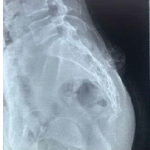

Differentiated thyroid carcinoma (DTC) accounts for a small proportion of all malignancies but is among the cancers most frequently associated with bone metastasis, especially in the axial skeleton. Metastatic involvement of the appendicular skeleton is rare, and pathological fractures of the femoral shaft are even more uncommon. Follicular thyroid carcinoma (FTC), due to its angioinvasive nature, shows a markedly higher propensity for hematogenous spread to bone than papillary thyroid carcinoma. These lesions significantly impair mobility and quality of life, often necessitating surgical intervention when life expectancy is reasonable. We describe a rare case of a 45-year-old male with metastatic FTC who presented with a pathological fracture of the femoral shaft. After multidisciplinary evaluation, the patient underwent wide segmental resection of the diseased femur, followed by intramedullary interlocking nailing with polymethylmethacrylate (PMMA) cement augmentation. This strategy provided immediate structural stability, allowed early weight-bearing, and offered potential cytoreductive benefit from PMMA-induced thermal effects. Postoperative recovery was uneventful, with significant pain relief and restoration of full function within 6 weeks. At 2-year follow-up, the patient remained ambulatory without limitations, with stable local control and ongoing oncological management. This case highlights that aggressive surgical management with stable reconstruction can yield excellent functional outcomes in selected patients with metastatic FTC, particularly when presenting with pathological fractures of weight-bearing bones. Durable fixation, early mobilization, and individualized multidisciplinary planning are crucial in optimizing quality of life in advanced thyroid carcinoma with skeletal metastases.